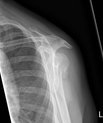

Conservative treatment with a sling can replace surgery for shoulder fractures

An arm in a sling cures a shoulder fracture just as well as an operation with plates and screws. This is shown by a comprehensive study from Aarhus…